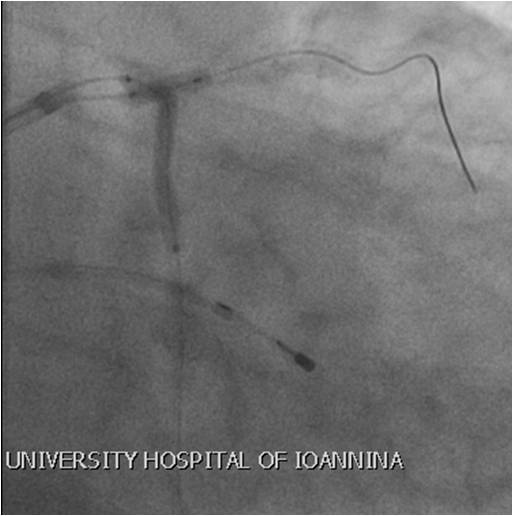

- Αγγειακή πρόσβαση και προετοιμασία στο αιμοδυναμικό εργαστήριο – Τοποθέτηση ενδοαορτικού ασκού (IABP) και προσωρινού βηματοδότη (TPW)